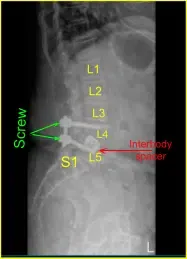

Un paciente que previamente había sido sometido a una fusión intersomática lateral L4/5, pero que acabó desarrollando radiculopatía grave en la pierna izquierda y luego radiculopatía moderada en la pierna derecha, asociada a un síndrome piriforme severo.

Dada la osteoporosis y nuestra preocupación por la estabilidad en L4/5 con fracturas de la placa terminal en el implante anterior L4/5, consideramos una fusión instrumentada. El paciente dio su consentimiento informado, comprendiendo todos los riesgos, beneficios y alternativas a la cirugía.

Dada la preocupación por el implante en posición prona y la sensación de que las placas terminales podrían haberse fracturado más, expusimos los procesos transversales de L4 y L5 y usamos el taladro para crear agujeros piloto en el pedículo del lado izquierdo en L4 y L5. Bajo fluoroscopia, guiamos las sondas a través de los pedículos y tocamos cada pedículo, luego colocamos tornillos pediculares en L4 y L5.

Estos tornillos se estimulaban y se comprobaban mediante fluoroscopia, luego se colocaba una roda y se apretaban finalmente los tornillos de tapa. En el lado derecho e izquierdo, decoricamos las facetas y procesos transversales y colocamos nuestra masa de fusión para la artrodesis.